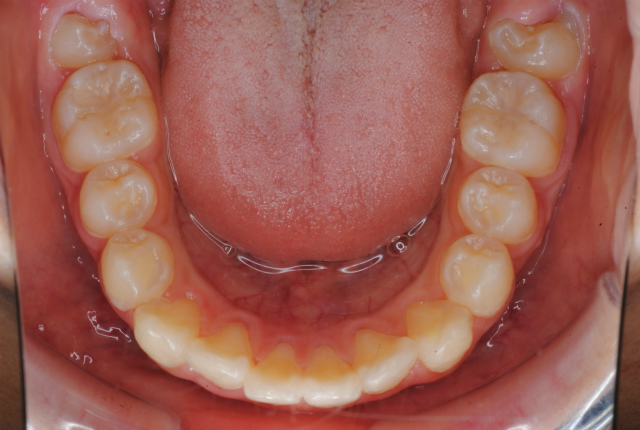

初診 下顎の歯並びの状態

現在 舌挙上のトレーニング中